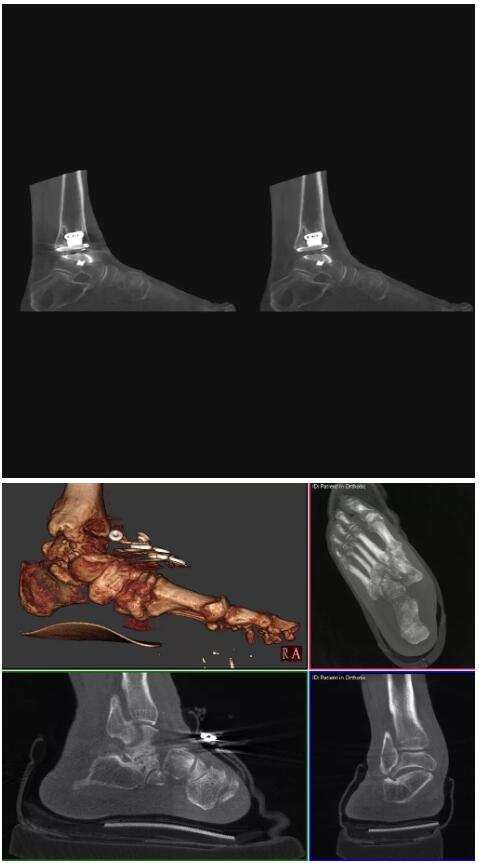

比如上面這款專用于足部和踝部掃查的CT成像系統(tǒng),患者在進行CT掃查時只需要站在上面即可,雙腳站或者單腳站都可以,當然,如果患者不是那么方便站著做完CT掃查,也可坐在上面。

這款CT掃查系統(tǒng)自帶屏蔽裝置,它的體積非常小,僅需要極小的空間即可,并不像常規(guī)CT那樣需要一間單獨的檢查室。此外,這種CT掃查的速度非??欤瑑H需30秒左右可以完成檢查,輻射劑量相對常規(guī)的CT要少許多,尤其適合醫(yī)院的骨科使用。

而患者站著做足部或者踝部做CT檢查還有個好處是,可以檢查患者在負重的情況下,骨關節(jié)的真實情況,而躺著做CT掃查時未必能看出來。負重CT掃查特別是對于受傷的運動員或者舞蹈員來說意義更大,能夠更準確地評估傷情,幫助他們盡早復原。

以上介紹的CT均來自國外同一家公司,這些CT均配置了可視化軟件,可以進行切片、3D重建以及大型CT附帶的所有典型的操作功能。

以下是這些“特立獨行”的CT所拍出來的圖像: